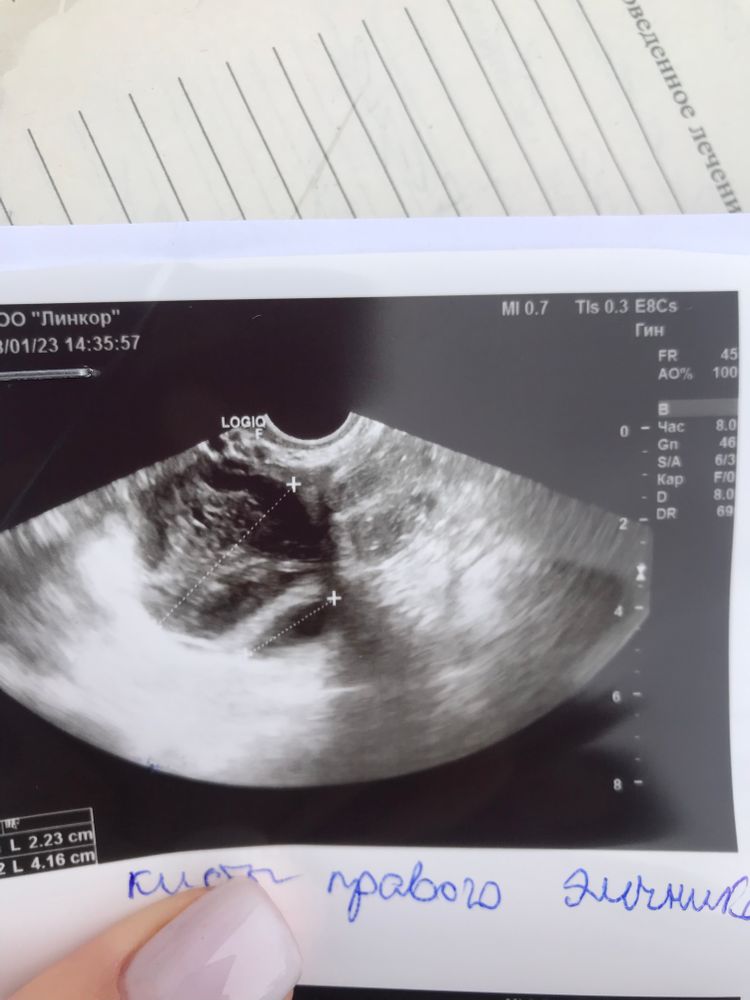

Здравствуйте девочки. У меня сегодня 21дц и две кисты жт 2см и 4см в одном яичнике🤣

Моя узист меня уверяла, что одна киста осталась после беременности, а вторая из этого цикла, но я уверена, что в начале цикла у меня не было кист, так как я ходила на узи на 10дц и там фолликулы были 8-9мм в обоих яичниках. Она посмотрела мое старое узи и сказала что то вроде «такого быть не может…как киста так выросла за 10 дней?». Я сама не знаю, но мне вот интересно, когда ждать кд? Девочки, расскажите пожалуйста ваши истории с циклами, в которых была киста или кисты жт, на сколько кд задержались или как-то лечили кисты? Пойду на узи еще раз теперь в субботу.

DamoCHka, у меня первый цикл после зб, гормональные сбои ожидаемы, просто не пойму, то ли она ошиблась на счет двух кист или хз что происходит, дф был один на 17дц 21,6мм. Сейчас это киста 4см и типа рыдом вторая 2см